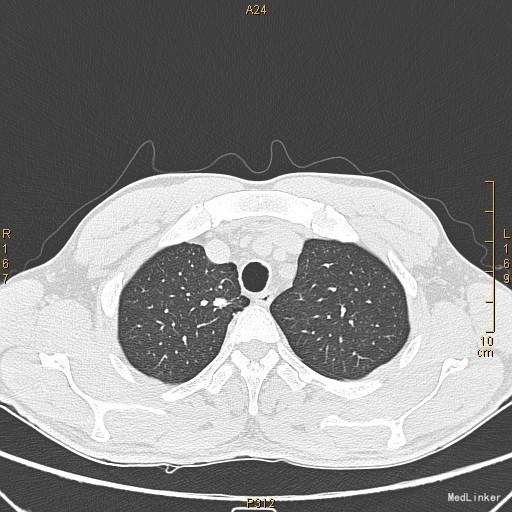

主诉:左眼睑下垂1年,加重半年。病史:患者1年前无明显诱因出现左眼睑下垂,抬起困难,伴视物重影,无言语不能、吞咽困难,无发热、头痛、恶心、呕吐、头晕、视物旋转、肢体麻木、饮水呛咳、视物模糊、肢体不自主运动、肢体抽搐、意识障碍、大小便失禁,休息后缓解,未予重视,半年来上述症状反复加重,10余天前至当地医院就诊,查新斯的明试验阳性,遂至我院神经内科就诊,胸部CT示:1、右肺尖钙化结节;2、胸腺增生。为了进一步治疗门诊拟“重症肌无力”收住我科。患者自起病以来,无发热、咳嗽、尿频、尿急、腹泻,无心悸、胸闷等,精神、食欲、睡眠好,体重无明显变化。

查体:左侧眼睑下垂,右侧眼裂宽10mm,左侧眼裂宽5mm。肺部查体未见异常。 辅查:新斯的明试验阳性。胸部CT示1、右肺尖钙化结节;2、胸腺增生。

该患者诊断“1.重症肌无力,眼肌型;2.右上肺钙化结节”明确,重症肌无力合并胸腺增生或胸腺瘤,有手术指征,我们为患者行胸腔镜下胸腺扩大切除术+右肺上叶楔形切除术。术后病理示:右上肺结节呈干酪样坏死,考虑结核。胸腺及纵隔脂肪均见淋巴增生。术后效果明显,患者左侧眼睑下垂较前好转,右侧眼裂宽10mm,左侧眼裂宽8mm,视物重影症状消失。